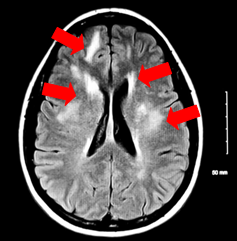

Description of Image 1

MRI scanning of patient before treatment

White spot indicate brain lesion (brain damage) area